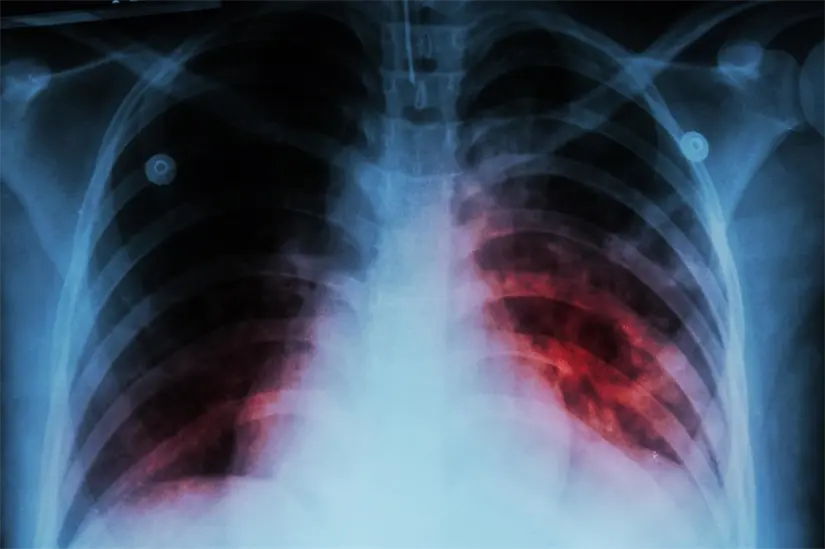

La tuberculosis es causada por una bacteria que afecta principalmente a los pulmones y se transmite por vía aérea. Entre sus síntomas están la tos crónica, fiebre, sudoración nocturna y pérdida de peso. Aunque es curable con tratamiento, puede ser grave si no se atiende oportunamente.